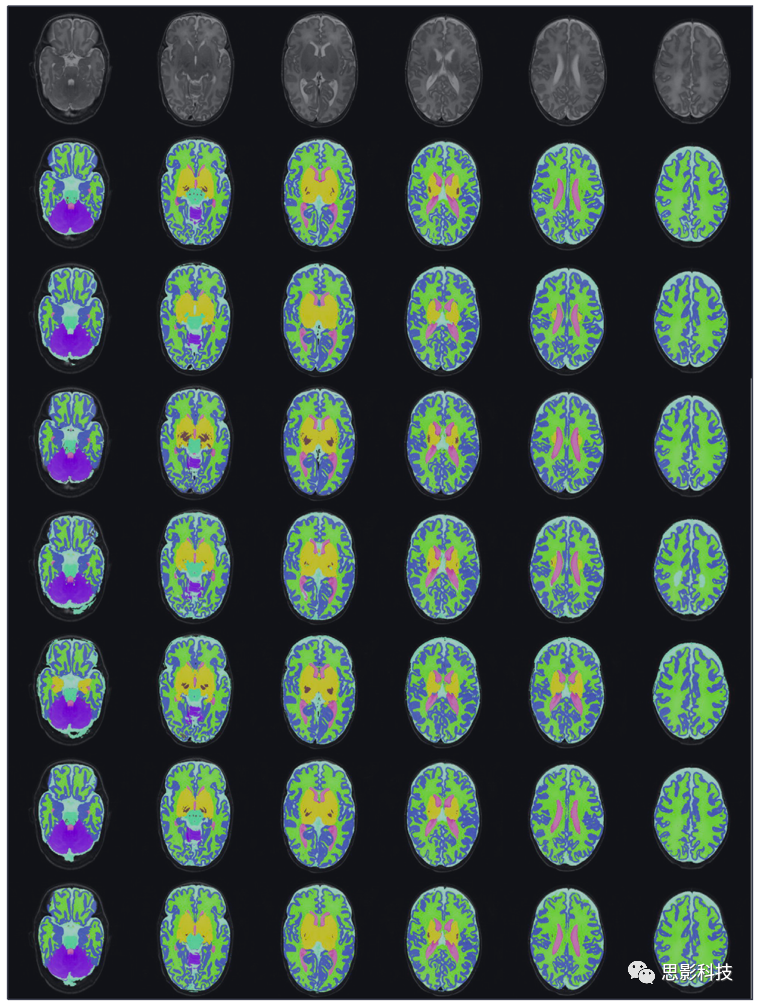

在新生兒分割領(lǐng)域的研究主要集中于腦MR圖像的組織分割。本節(jié)介紹文獻(xiàn)中用于新生兒組織分割的方法。圖7給出了不同組織類型的分割示例。

使用Draw-EM的新生兒MRI的組織分割示例。